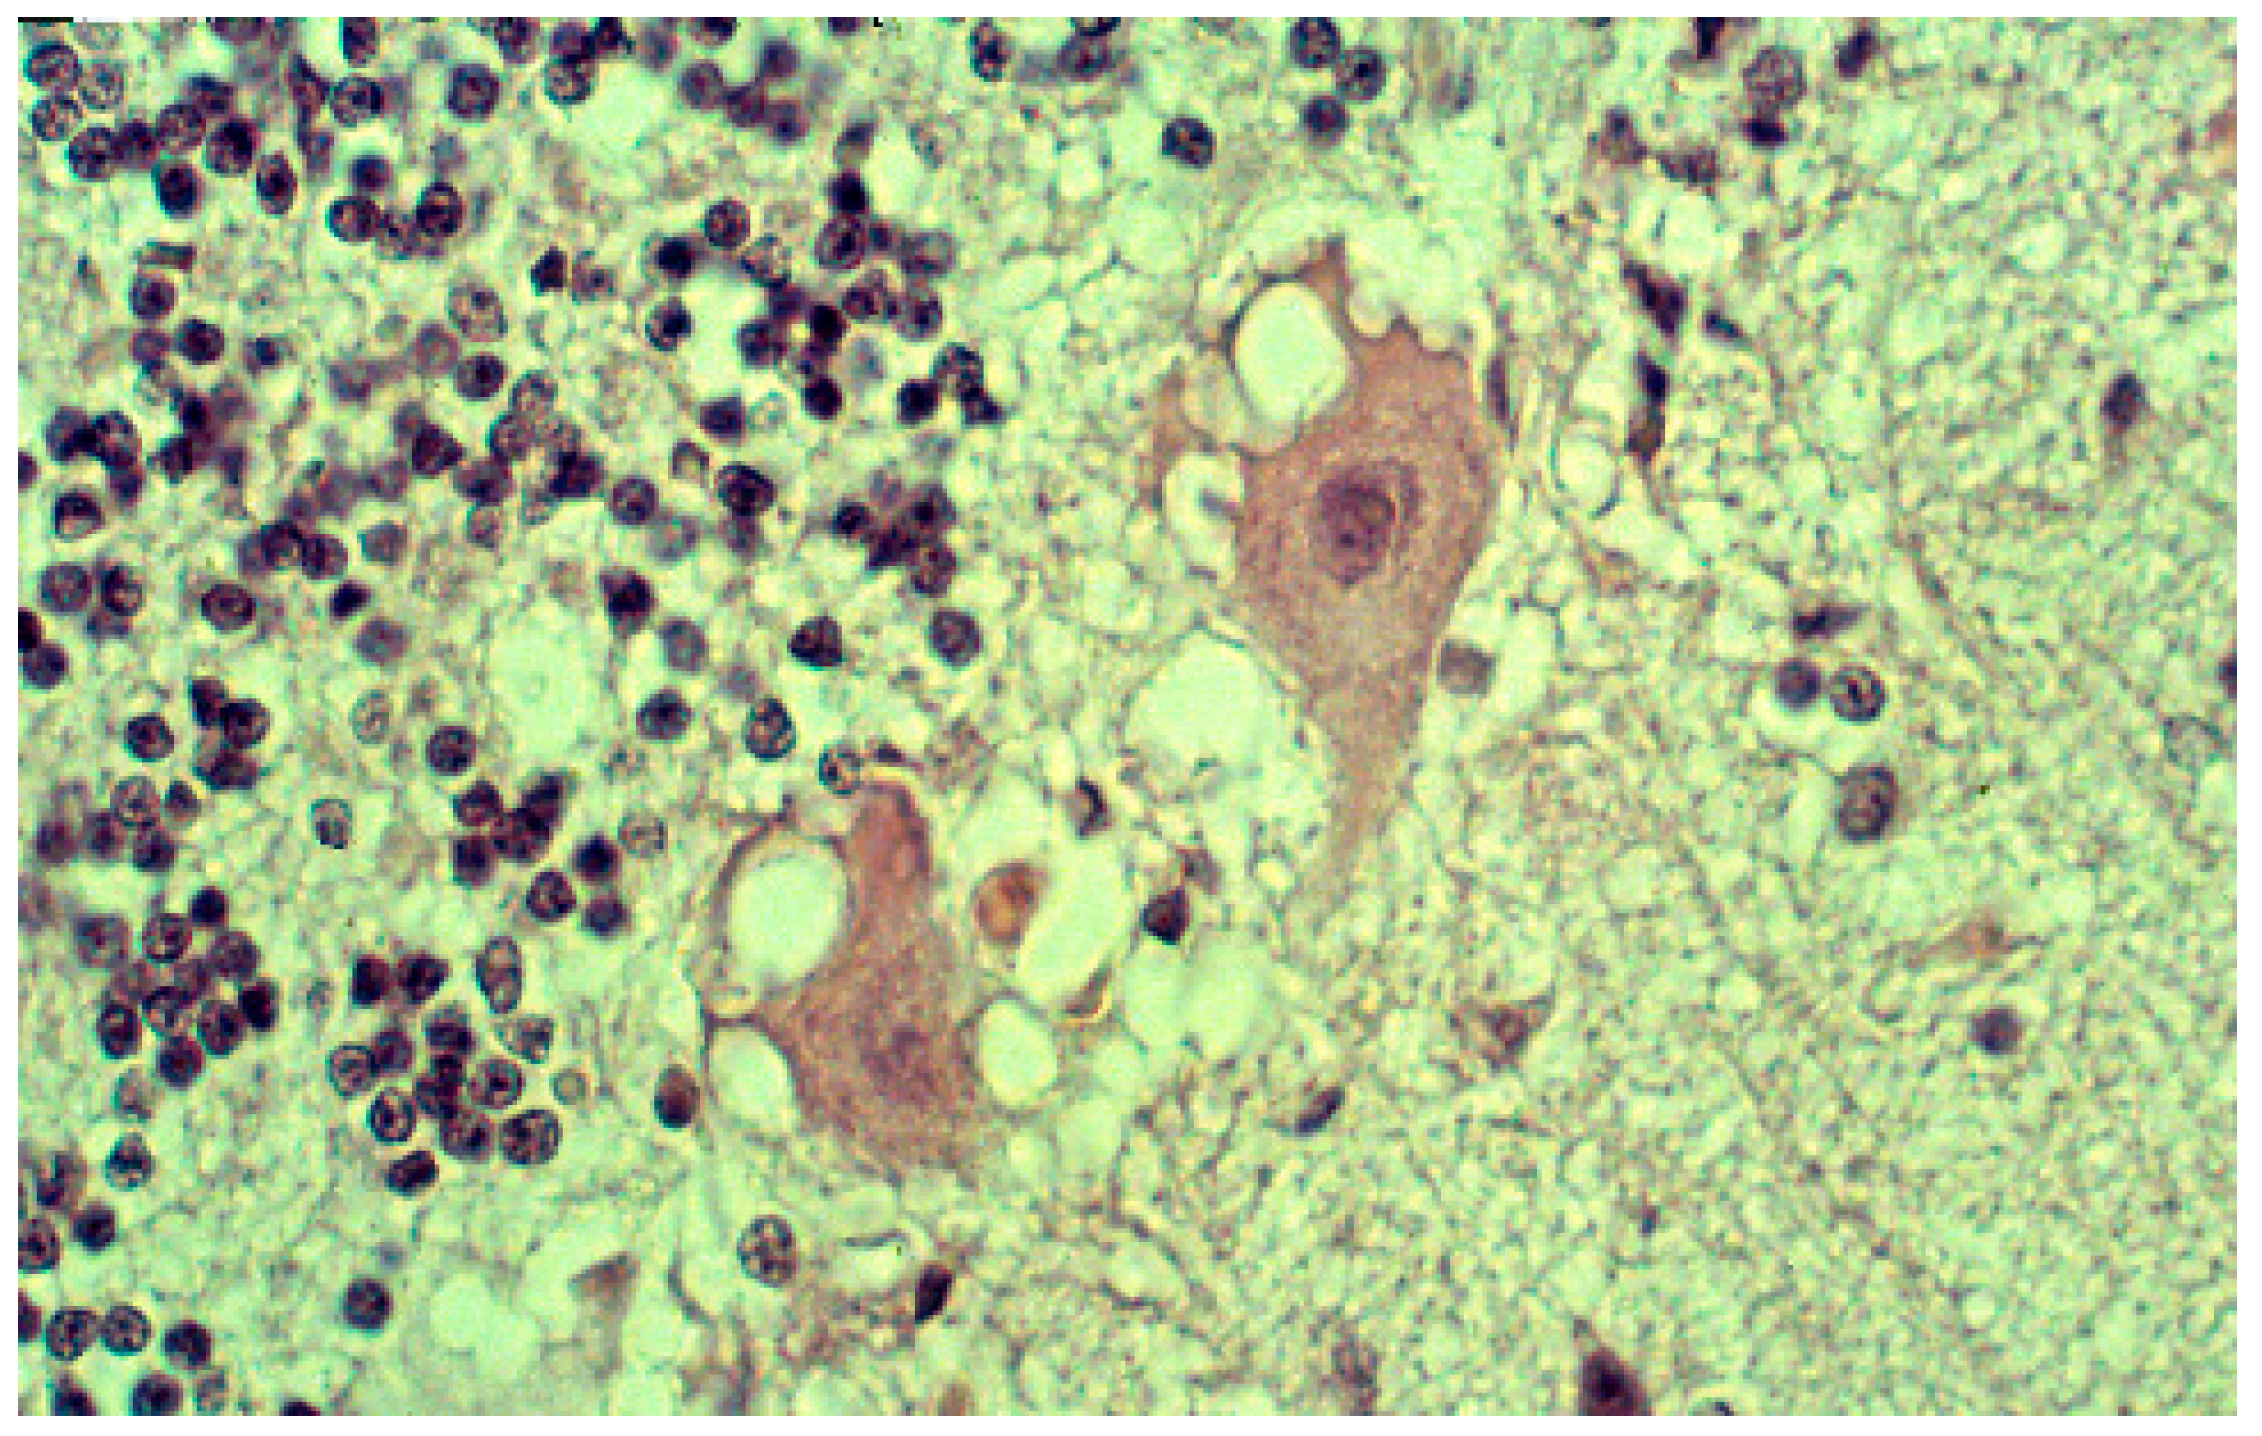

The most striking neuropathologic feature of kuru was the presence of numerous amyloid plaques found in six of 12 cases studied by Klatzo et al. [124,125], and in “about three-quarters” of the 13 cases of Beck and Daniel [106,107,108,109,110]; they became known as “kuru plaques” (Figure 16a–f) [126,127,128,129,130,131,132].

Figure 16.

(a) Typical kuru plaque stained silver. Courtesy of D. Carleton Gajdusek; (b) a linear row of kuru plaques probably attached to a neurite; (c) a kuru plaque stained with Alzian blue (41-93-2a-alcian-20-17-alcian). Courtesy of D. Carleton Gajdusek; (d) A kuru plaque and PrPSc deposits surrounded by glial cells in the human cerebellum. Confocal laser microscopy, prion protein (clone 12F10, Alexa Fluor 488)—green, GFAP (polyclonal rabbit, AlexaFluor 546)—red, magnification 600×, digital zoom 2.1×. Three-dimensional reconstruction with surface rendering. (e) Electron microscopic image of the kuru plaque, material reversed from paraffin, 13,000×; (f); higher magnification to show bundles of kuru plaque-fibrils, 50,000×.

Plaques had a diameter of 20–60 μm, were of round or oval in shape, and consisted of a darker core with subtle radiating periphery enveloped by a pale “halo”. Kuru plaques were most common in the granular cell layer of the cerebellum, basal ganglia, thalamus, and cerebral cortex in that order of frequency. Kuru plaques are metachromatic and stain with PAS, Alcian blue, and Congo-red, and are weakly argentophilic when impregnated according to Belschowsky or von Braunmühl techniques. Of historical interest, another unique disease reported by Seitelberger [133] as “a peculiar hereditary disease of the central nervous system in a family from lower Austria” (germ. Eigenartige familiar-hereditare Krankenheit des Zentralnervensystems in einer niederoosterreichen Sippe) was mentioned by Neumann et al. [134], who was, thus, the first person to suggest a connection between kuru and Gerstmann-Straüssler-Scheinker disease. Indeed, the latter was transmitted to non-human primates in 1981 [135].

Immunohistochemical studies revealed that misfolded PrPSc was present not only as kuru plaques but also in synaptic and perineuronal sites (Figure 16a–f) [129,137], and, in the spinal cord, the substantia gelatinosa was particularly affected, as in iatrogenic CJD cases following peripheral inoculation [143]. Brandner et al. [144] studied one of the very last cases of kuru and basically confirmed the findings of Hainfellner et al. [137]. The latter case was neuropathologically compared with known subtypes of CJD and it seems the most similar to type 3 129 MV type of CJD of the Collinge et al. [145] classification or type 2 CJD of the Parchi et al. [146] classification [147]. Of note, immunocytochemistry with 12F10 antibodies revealed a stronger signal than that using 3F4 anti-PrP antibodies [146].